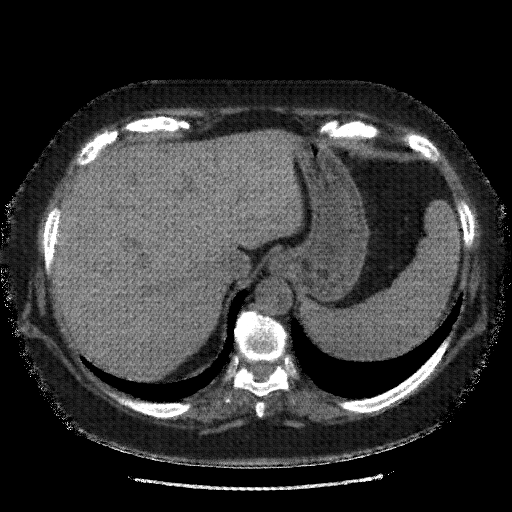

Reconstructed NATIVE CT scan (cycle consistency)

Full window (WL 1023.5, WW 4095 β†’ Low βˆ’1024, High +3071)

Lung window (WL -600, WW 1500 β†’ Low βˆ’1350, High +150)

Mediastinum window (WL 40, WW 400 β†’ Low βˆ’160, High +240)